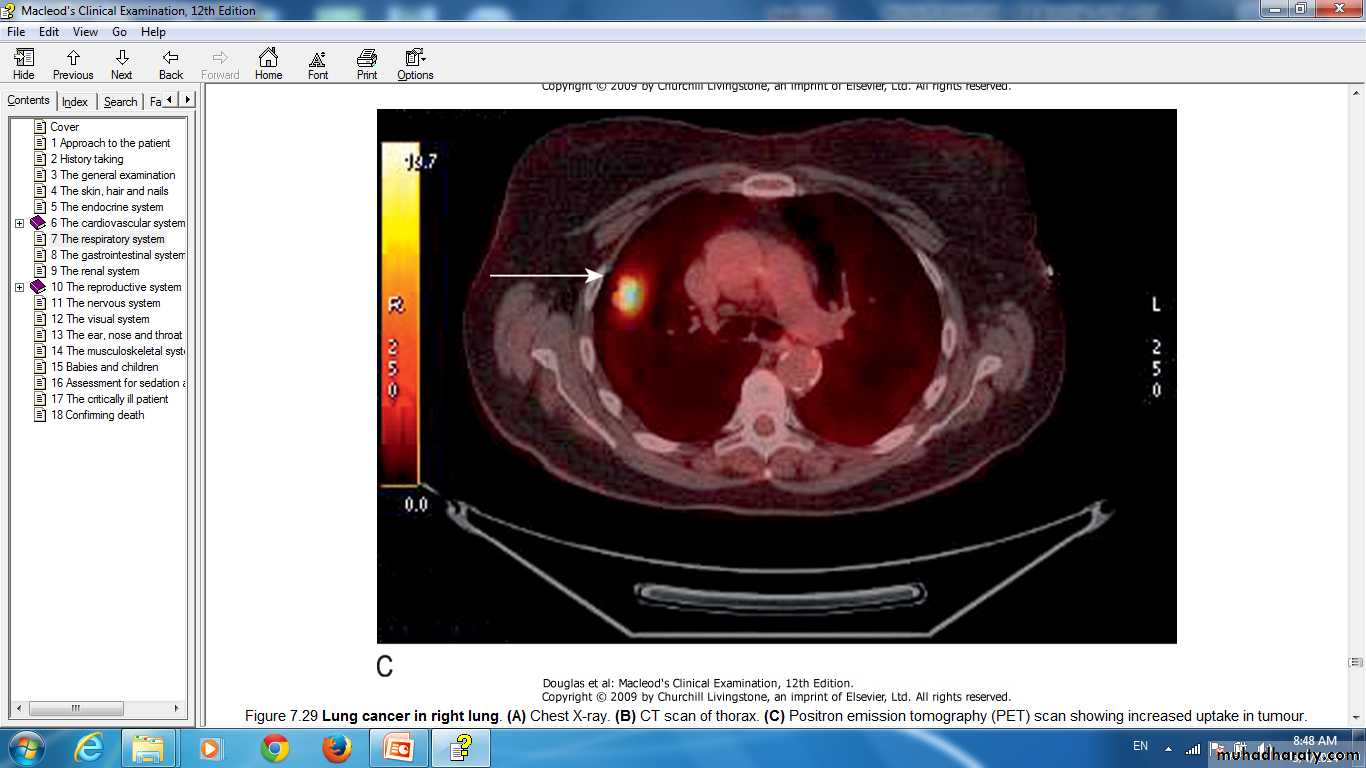

Lung cancer in right lung Positron emission tomography (PET) scan showing increased uptake in tumour